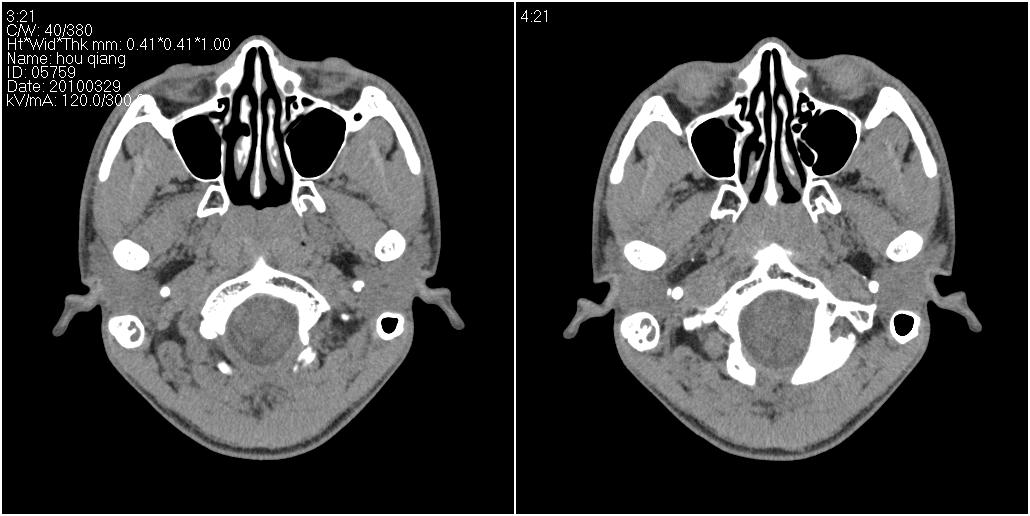

标题: CT25419:男性,18岁。右耳肿、痛5个多月。 [打印本页]

标题: CT25419:男性,18岁。右耳肿、痛5个多月。

右侧中耳乳突炎累及外耳道,鼻咽腺样体肥大。

1)右侧慢性中耳乳突炎并右侧中耳腔及外耳道肉芽肿或胆脂瘤形成。2)鼻咽腺样体肥大。